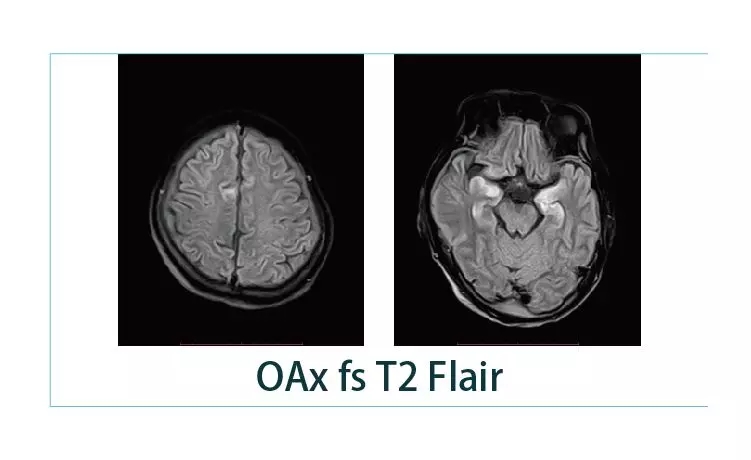

【朗润影像档案】20190125磁共振影像病例结果讨论

1548727074790396.jpg1548727094576003.jpg1548727106975217.jpg1548727127776211.jpg